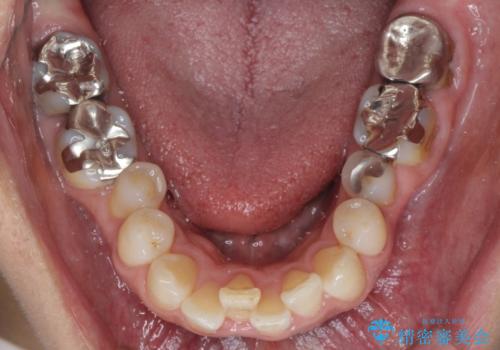

- 上下の奥歯にものが挟まりやすいことを気にして来院された患者様です。

上下ともに、やや大きいむし歯があり、そこにものが挟まりやすくなっていました。

下の奥歯も、虫歯を取り除いて仮歯を装着したことで歯肉の腫れが引き、出血することもなくなりました。